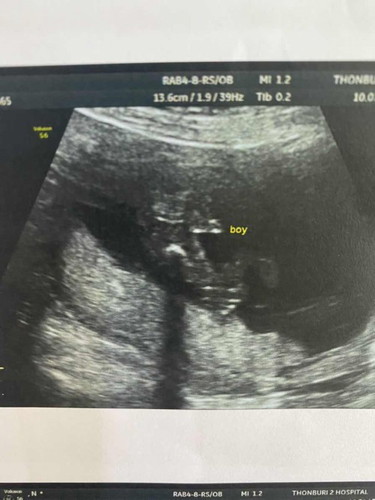

ตรวจคัดกรองดาวน์ซินโดมกันราคาเท่าไหร่คะ ส่วนตัวตรวจราคา 15900 แต่คุณหมอแนะนำดีมาก ผลออกมาปกติทุกอย่าง แถมจู๋น้อยมา 1 คน😂